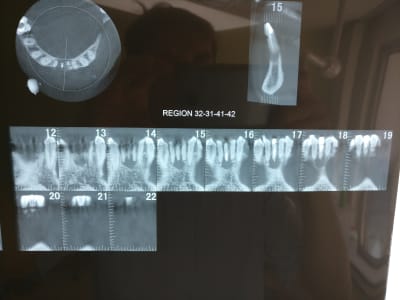

Ci joint le cône beam

Mais surtout que pensez vous de ce qu'on voit sur les coupes 31 et 38? Morceaux de racines ? lors de l'exo faut les virer aussi? voir même extraire 41 et 32?

En fait, ce qui m'a induit en erreur, c'est la coupe 15 du doc 3, je ne comprends pas son orientation. L'image est très différente des coupes du doc 4.

D'ailleurs, c'est une 41.

Je pense que j'ai compris, je pense que tu devrais trouver le second en linguo distal.

Pour les apexs (?), la lésion ne semble pas centrée dessus. Si résection, peut-être devras tu alors les virer et faire 2 endos supplémentaires...

Recherche ce canal supplémentaire avant. (disto lingual!)

A la base je pense qu'il y avait un second canal en lingual. Regarde les coupes horizontales tu devrais le trouver ou au moins l'imaginer. Sur les coupes sagittales, le canal que tu as obture est deporte en vestibulaire, c'est une bonne indication. Sur la retro tu vois bien les deux racines de l'incisive latérale, tu trouves en general 2 canaux sur la centrale dans ce cas la.

Je vois de plus en plus souvent des incisives et canines mandibulaires avec 2 racines (encore une 33 traitée il y a 15 jours avec 2 racines chez une dame de 82 ans, chez qui j'ai précédemment retraitées les 42 et 32 à 2 racines avec infection apicale aujourd'hui totalement rentrés dans l'ordre).